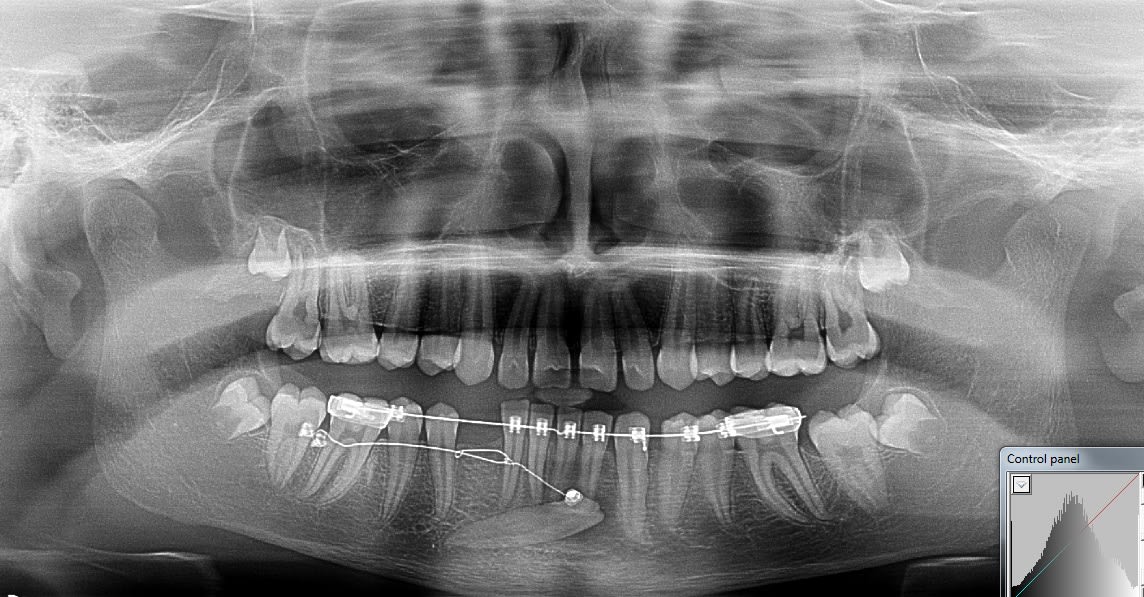

Voici un exemple de traction de canine incluse inférieure. Il faut absolument laisser les incisives inférieures totalement libres pour qu'elles puissent un peu se déplacer spontanément si nécessaire.

La supériorité du CT8 sur n'importe quel autre ancrage pour tracter les canines incluses tient en particulier à sa longueur qui permet des forces légères (25g), avec une grande amplitude de mouvement en direction contrôlée. Prévois bien un retour du fil suffisamment long après sa pliure au niveau de la ligature pour avoir de la marge. Tu pourras alors le déplier et le replier différemment en cours de traitement si tu veux, un moment donné, modifier la direction de la force. On a en effet toujours tendance à le couper trop court.

Mon patient sort du cab a l'instant, avec un CT8 tout neuf.

La traction avec la chainette sur minivis avait deja initié le travail.

je mettrais les pano a mesure de l'avancement du traitement.

C'est assurément un beau fil et une belle boucle, mais es-tu sûr que tes vis vont tenir ? Elles me paraissent bien hautes par rapport à la ligne oblique externe où on les place habituellement.

Ca y est 8 mois plus tard j'ai put poser un bracket dessus :-) .

Pour ton cas ça devrait aller plus vite. Quand j'ai commencé ce cas je n'avais pas le bon matériel disponible ( aujourd'hui ça serait la technique à Dancha direct ) , j'ai bricolé différent stytem mais il y a eux de la casse et plusieurs réparation on était nécessaire.

Enfin gros plaisir quand j'ai collé le bracket sur cette dent.

Sur ce cas très honnêtement je n'avais pas imaginer que redresser cette canine prendrait si longtemps. Mécaniquement très simple du à la bonne position de l'apex, simple mouvement de tipping mais putain 2 ans ...